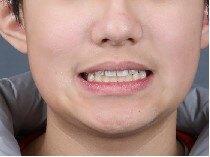

治疗后

- 治疗后2年

通过隐形矫治,序列化推上牙列向后,并适量扩弓,排齐内收上前牙,适量唇倾和片切排齐下前牙。

配合二类牵引,实现咬合跳跃,改善侧貌。